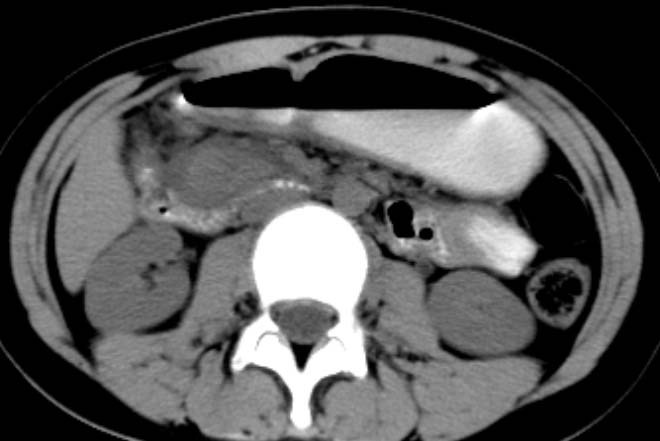

女,14岁。腹痛3天。腹部触诊未触及包块。碘剂阳性未增强。求助战友。。。。。。。。。。。

胰头部增大,周围模糊,有渗出,胰腺炎可能性大,建议结合化验检查;左侧输尿管上段略扩张.

1)急性胰腺炎。2)肝右叶后上段肝内胆管结石。3)左侧输尿管上段扩张,原因待查。

化验结果:血.尿淀粉酶正常。

既然实验室检查不支持炎症,那就强化或mr检查帮助明确吧.

支持:急性胰腺炎!血.尿淀粉酶正常那么mri检查一下。

病灶应在胰头下区,不一定是胰头,结合周边低密度水肿,是否可能为十二指肠(xi)室炎症或其它炎症。

胰周无明显渗出,吉氏筋膜未见增厚。血尿试验室检查不支持。排除胰腺炎。